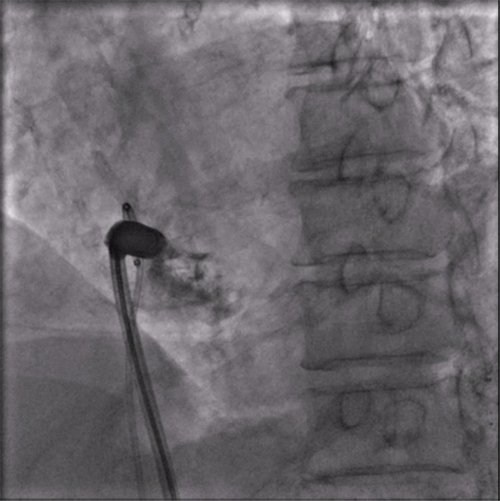

经过周密的术前准备,彭晖、孙志军两位主任带领邸北冰主治医师、柳晓娜主治医师和梁立丰医师在内的起搏电生理团队,于心脏介入手术室为患者实施手术。手术团队股静脉穿刺成功后,首先对下腔静脉进行造影并将外鞘放置送入下腔静脉,随后将新型主动固定螺旋无导线起搏器顺利跨瓣送入右心室目标位置,旋入前测试无导线起搏器各项电学参数良好,确认位置合适后旋入固定起搏器,在植入过程中动态测试起搏器各项参数以辅助判断固定程度,达到标准后进入对接栓模式,再次测试起搏器固定位置稳定、各项参数良好后释放起搏器,最后撤出鞘管,顺利完成手术。整个手术流程高效有序,医疗团队成员紧密配合,默契无间,仅耗时40分钟共同完成了这一具有挑战性的任务。

LAO造影确认指向间隔部